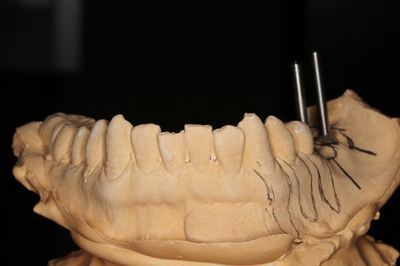

左下大臼歯部分に2本のインプラントオペを計画します。

いつものように事前にフェイスボウ トランスファー(顔弓測定)を行い

顎関節と上顎歯列の位置関係を決定します。

KaVo プロターevo7 咬合器に上下の歯列模型をマウントします。

CTデータと重ね合わせて、埋入位置・方向を決めます。

サージカルステント(ドリルガイド・ドリルスリーブ)を作製し

事前のシミュレーションを生かすように準備します。

すべてを私が行っています。